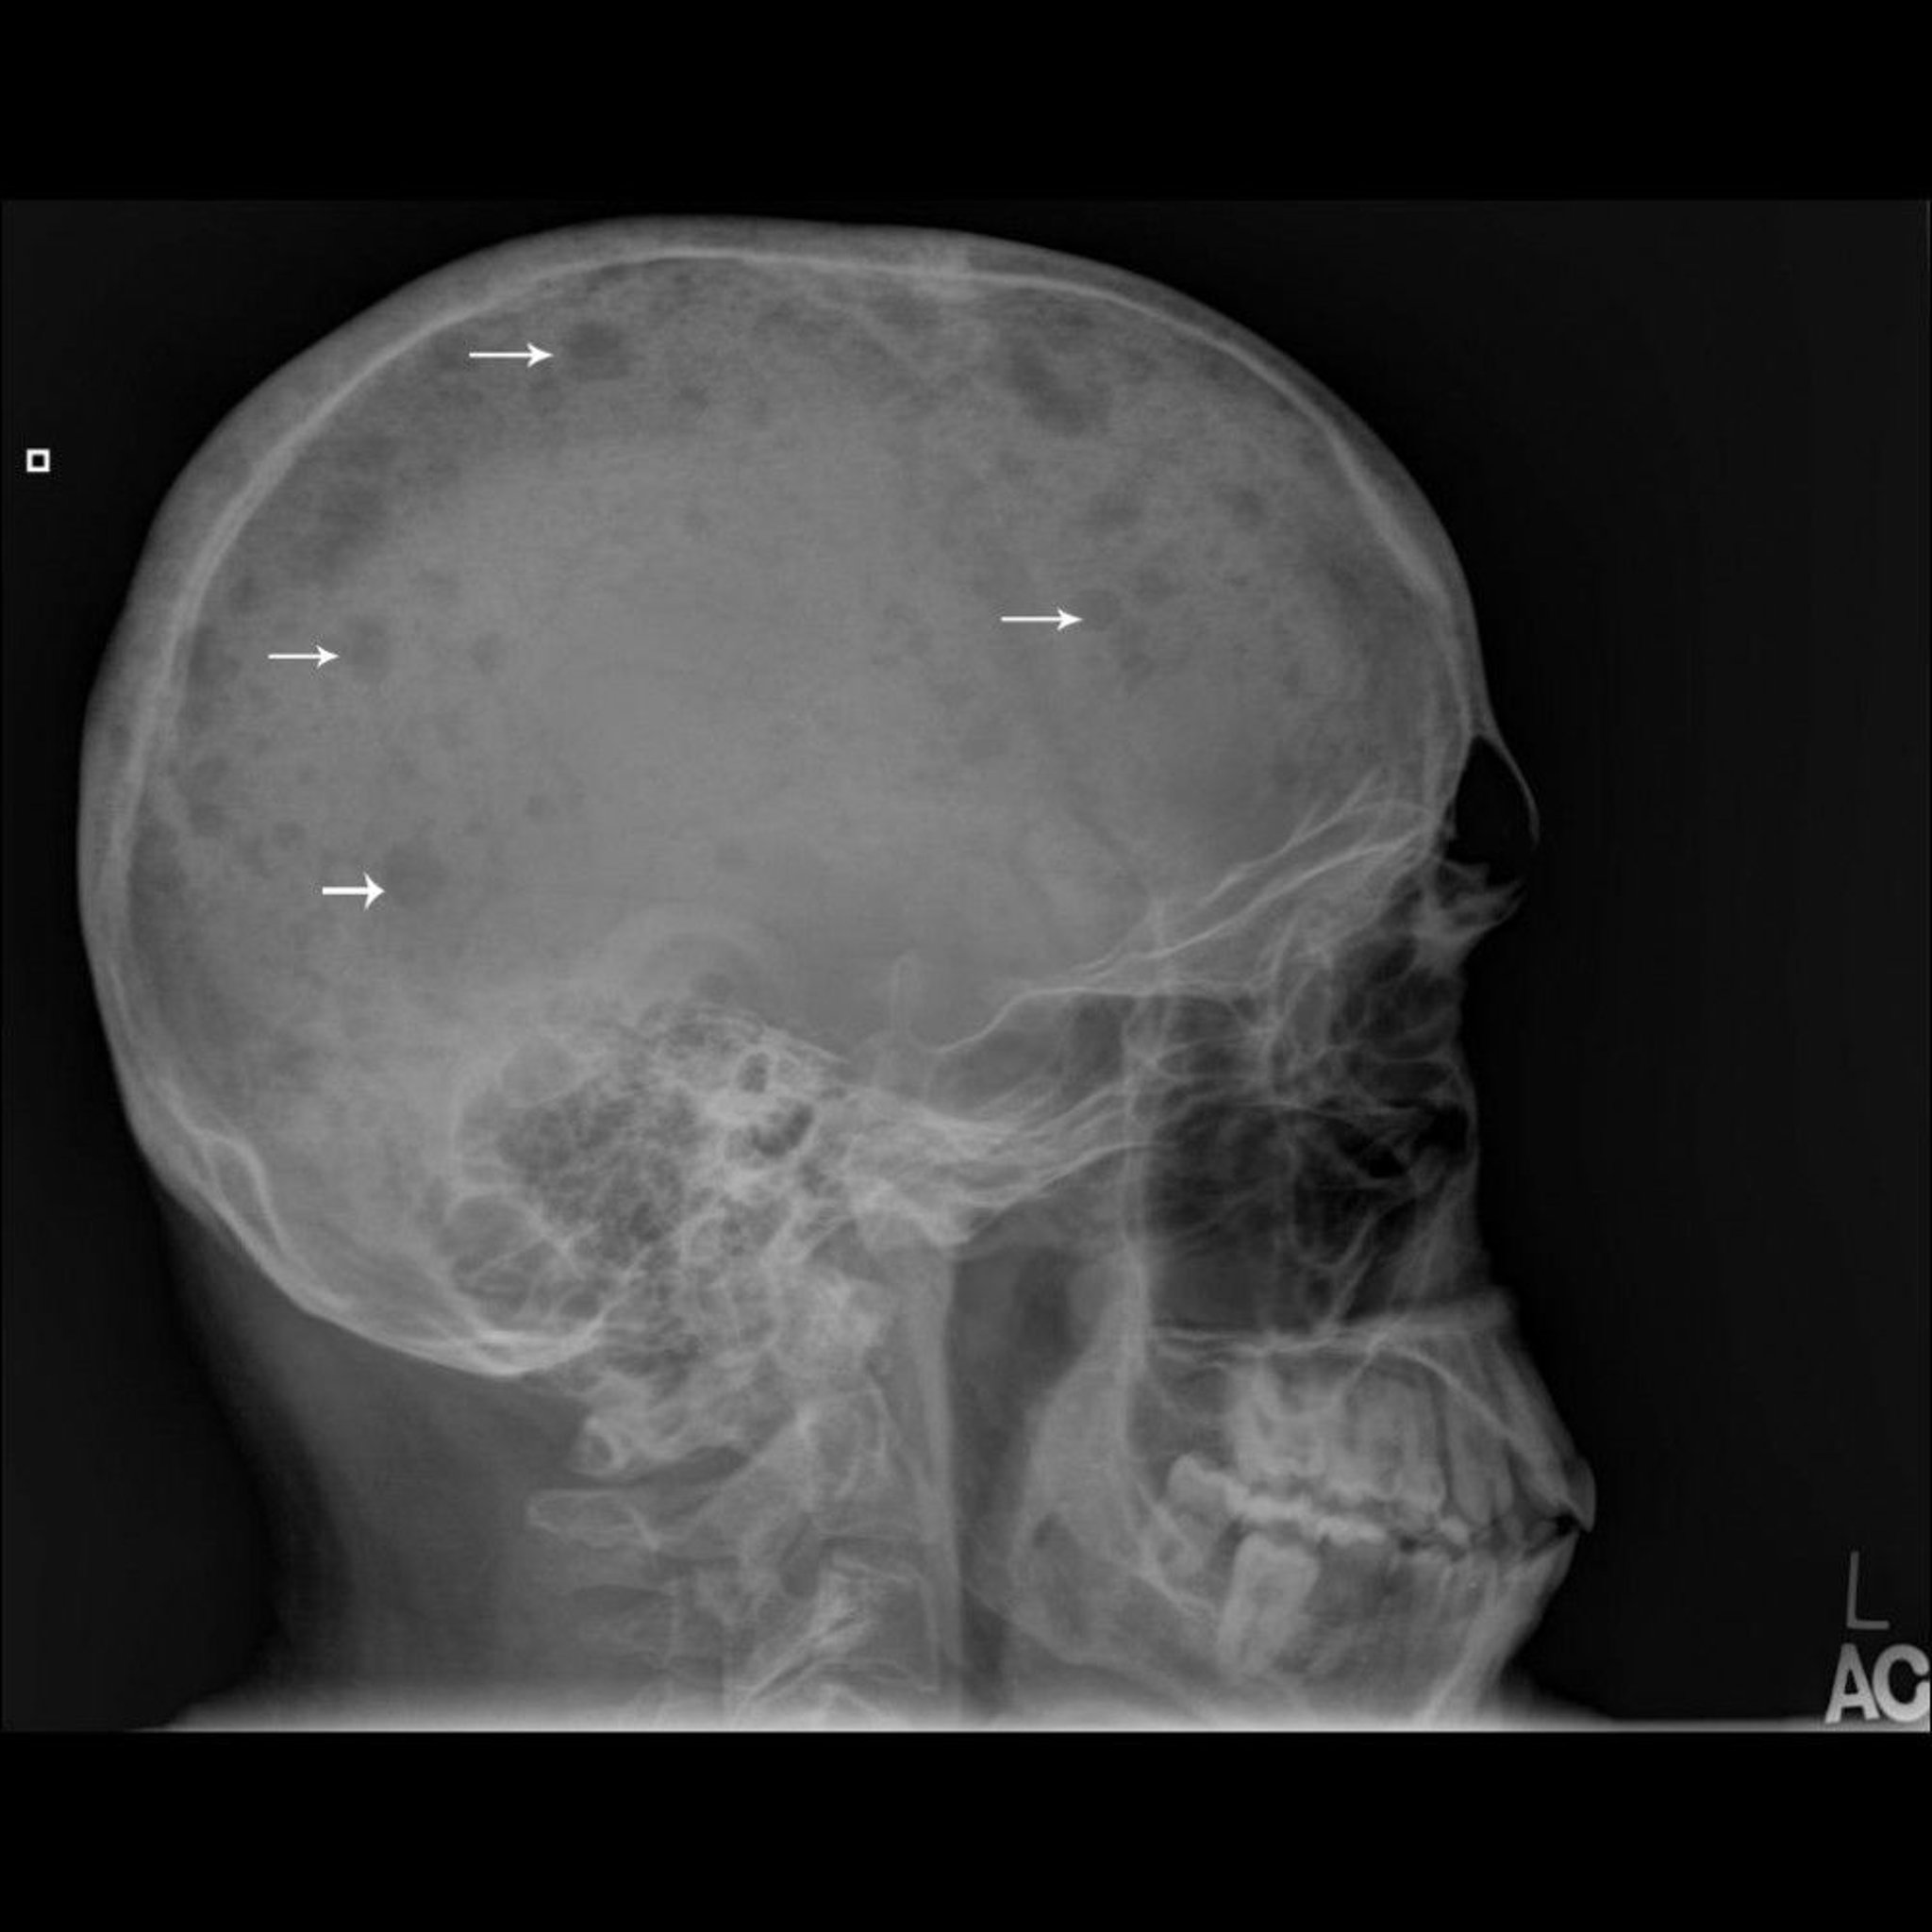

Myélome multiple

Cette radiographie du crâne montre des lésions multiples de l'os (flèches), typiques du myélome multiple.

Image courtoisie de Michael J. Joyce, MD, and Hakan Ilaslan, MD.